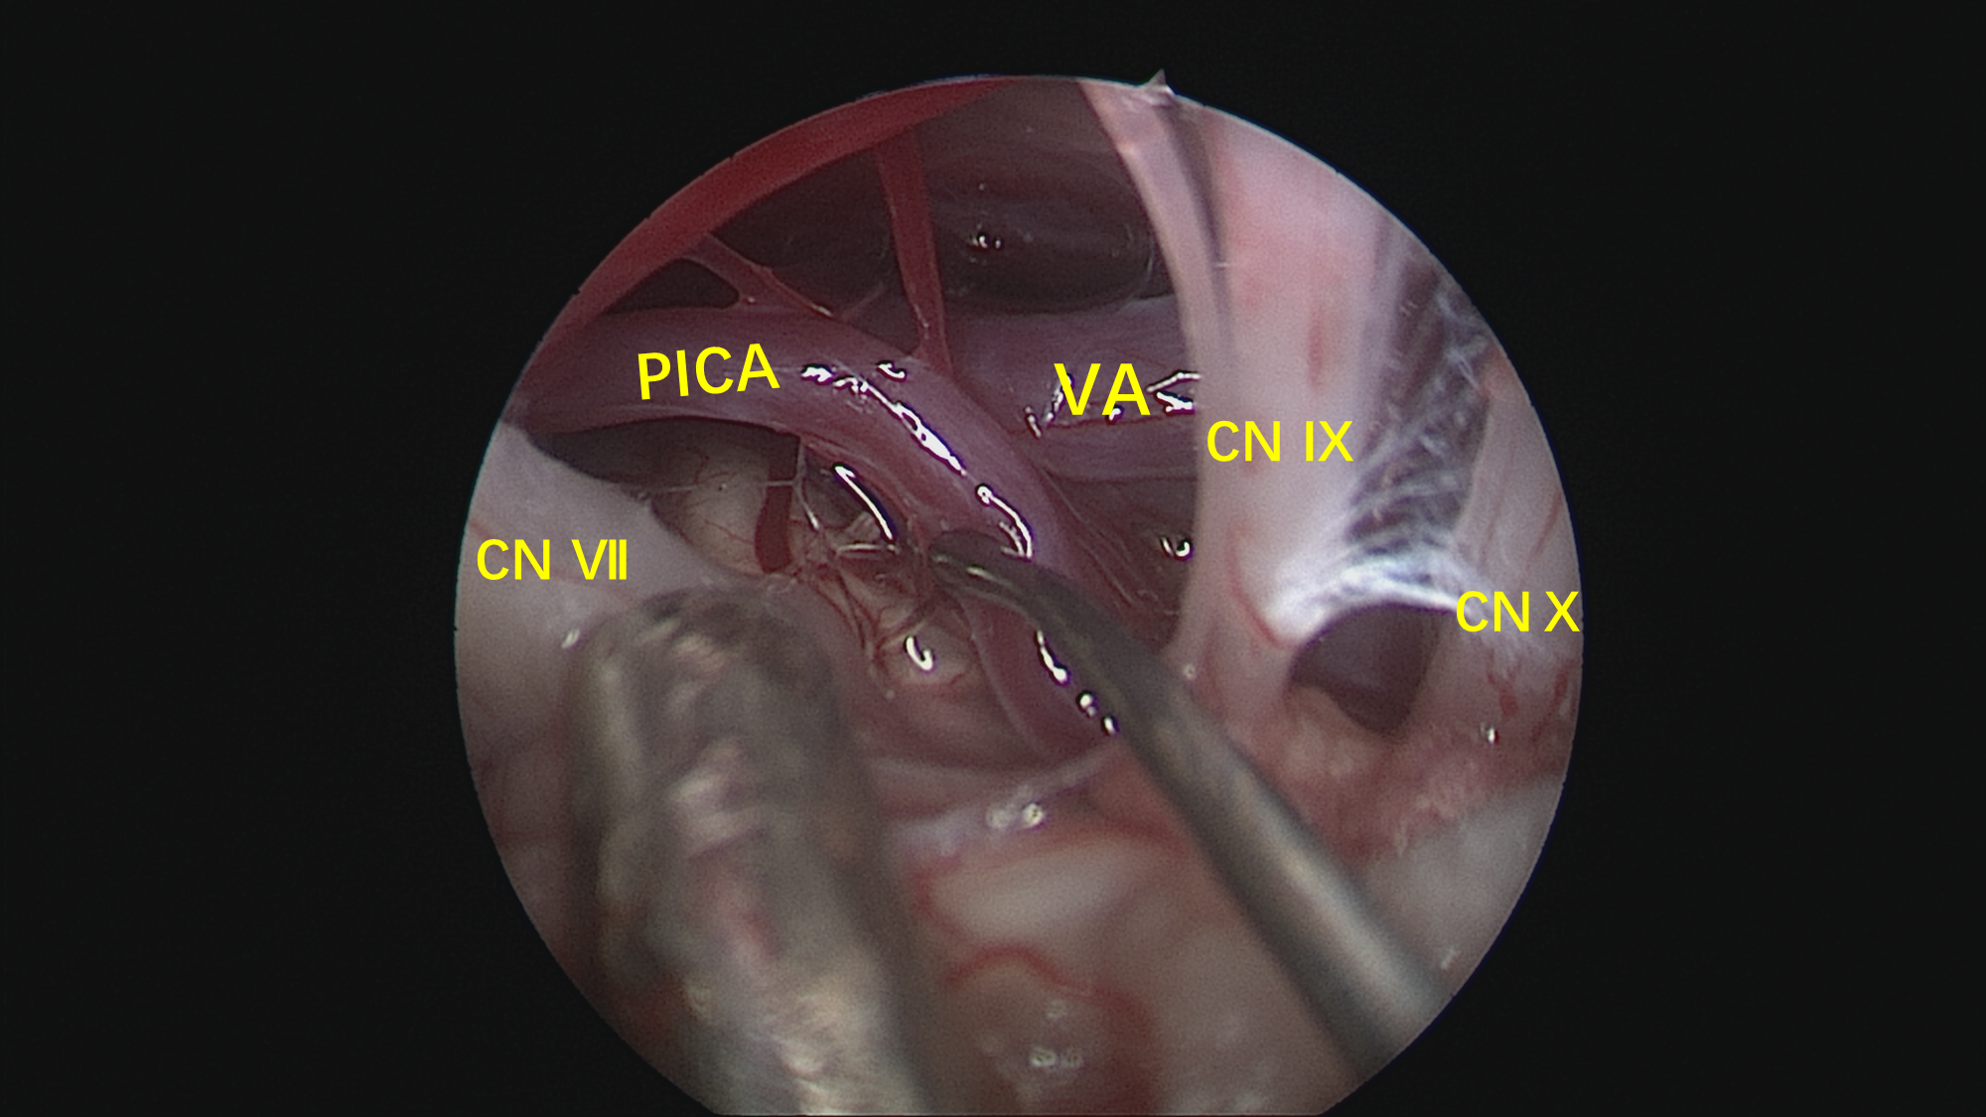

镜下:从面听神经与后组颅神经之间观察迂曲的小脑后下动脉。

神经内镜抵近观察,与术前影像一致,PICA从VA发出后于下方呈袢,压迫面神经出脑干处。

Tefflon垫绵充分减压。再次观察,PICA如我们所见,迂曲呈“S”型,再于后组颅神经后方(手术视角)绕回,与小脑后下动脉走行特点相吻合。